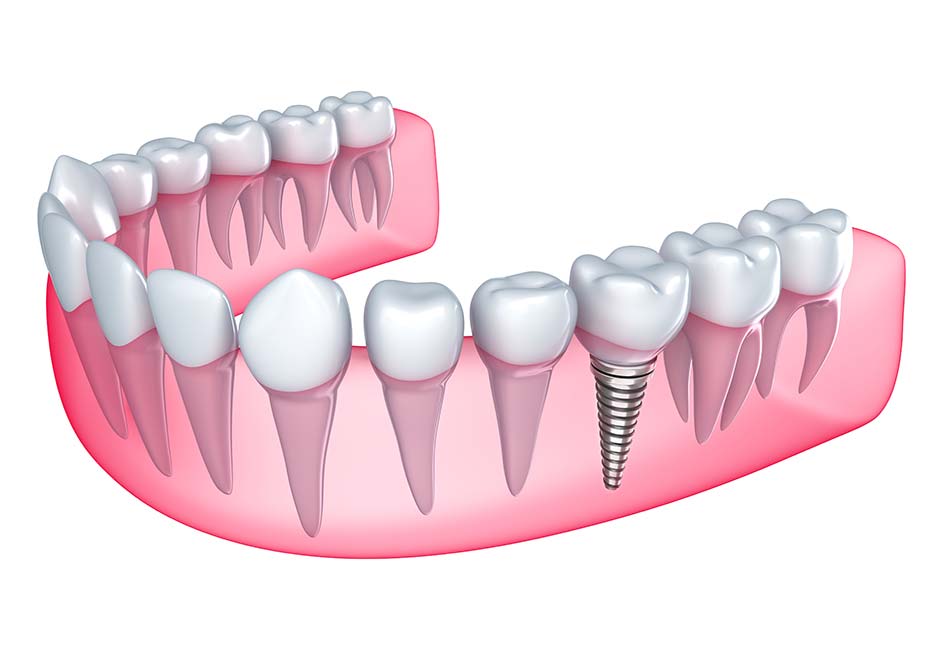

Placement of the Implant

If you’re a good candidate for dental implants near you, we’ll proceed with placing the dental implant. This involves a minor surgical procedure in which a titanium post is inserted into your jawbone. We use local anesthesia to ensure you’re comfortable throughout the process. Over time, the implant will fuse with the bone in a process called osseointegration, which typically takes a few months.

Attaching the Abutment

Once the implant has joined with the bone, a small piece called an abutment is attached. This abutment connects the implant to the new tooth. It sits above the gums and may need a small procedure to put it in place.

Fitting the Artificial Tooth

After the abutment is ready and your gums have healed, we’ll take a mould of your mouth to make a custom tooth (crown) that fits just right. The crown is then attached to the abutment, completing your dental implant.

1. What are dental implants?

Dental implants are titanium posts surgically placed into the jawbone to replace missing teeth. They act as artificial tooth roots and provide a stable base for attaching crowns, bridges, or dentures.